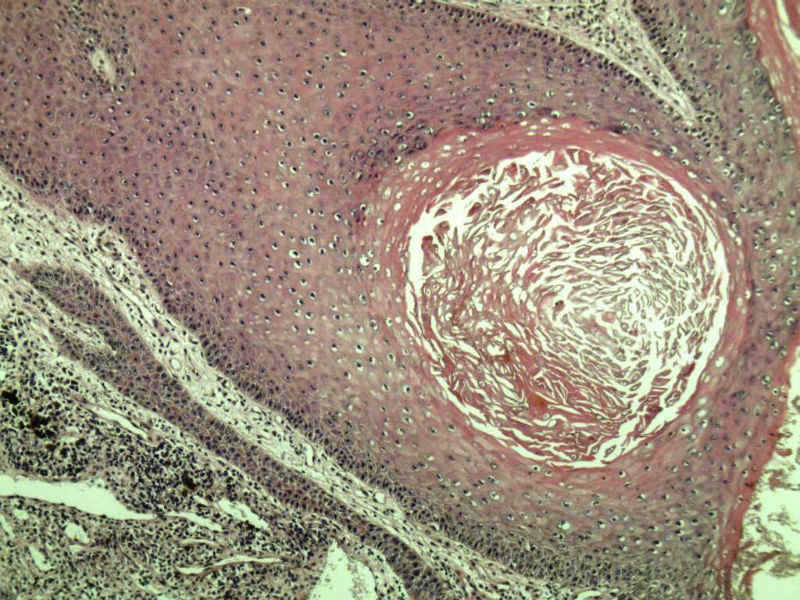

女 67岁 临床考虑面部色素痣 1*0.8 cm  请问各位老师 这是什么? 谢谢!面部包块图1

毛母/发细胞瘤鉴别基底细胞癌,可做CD10,CK7,CK20鉴别

考虑毛发上皮瘤,需除外基底细胞癌。

毛发上皮瘤,需与基底细胞癌鉴别

第一例:毛发上皮瘤

第一例:毛发上皮瘤,与基底细胞瘤区别明显。

第一例  毛发上皮瘤,和基底细胞癌鉴别一下

第一例考虑毛母细胞瘤,第二例考虑基底细胞癌。

毛母细胞瘤

第一例:毛母细胞瘤;第二例:基底细胞癌

第一例,毛发上皮瘤;第二例,基底细胞癌。

一毛发上皮瘤